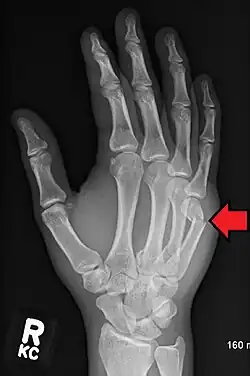

Boxer's fracture of the 5th metacarpal head from punching a wall

A boxer's fracture is the break of the fifth metacarpal bone of the hand near the knuckle.[4] Occasionally, it is used to refer to fractures of the fourth metacarpal as well.[1] Symptoms include pain and a depressed knuckle.[2]

Classically, it occurs after a person hits an object with a closed fist.[3] The knuckle is then bent towards the palm of the hand.[3] Diagnosis is generally suspected based on symptoms and confirmed with X-rays.[3]

Diagnosis by a doctor's examination is the most common, often confirmed by x-rays. X-ray is used to display the fracture and the angulations of the fracture. A CT scan may be done in very rare cases to provide a more detailed picture.